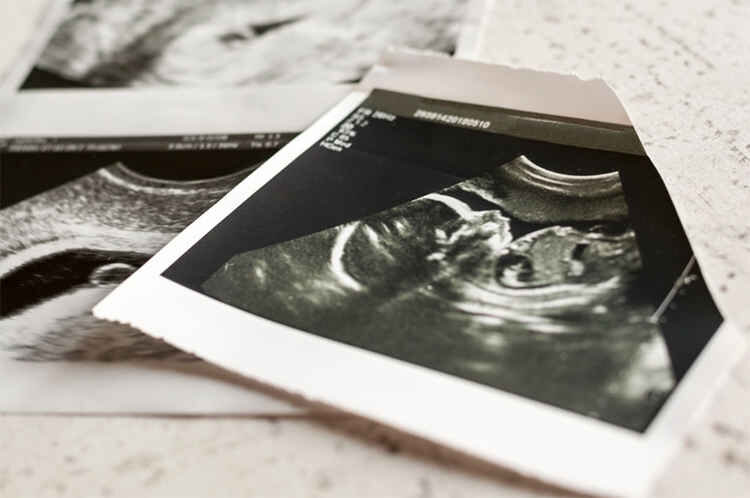

نتایج یک مطالعه نشان میدهد زنان بارداری که از رژیم غذایی مدیترانهای پیروی میکنند، احتمال کمتری دارد که نوزادی خیلی کوچک و کموزن به دنیا بیاورند.

سلامت- امیدبانوان؛ مهر به نقل از دیلی میل نوشت: دانشمندان اسپانیایی ۱۲۰۰ مادر باردار را تا نیمه دوم بارداری تحت نظر گرفتند. آنها در معرض خطر تولد نوزادی با وزن کم در نظر گرفته شده بودند.

نوزادانی که کوچک و با وزن پایین به دنیا می آیند با افزایش سن بیشتر از مشکلات رشد مغز و قلب رنج می برند.